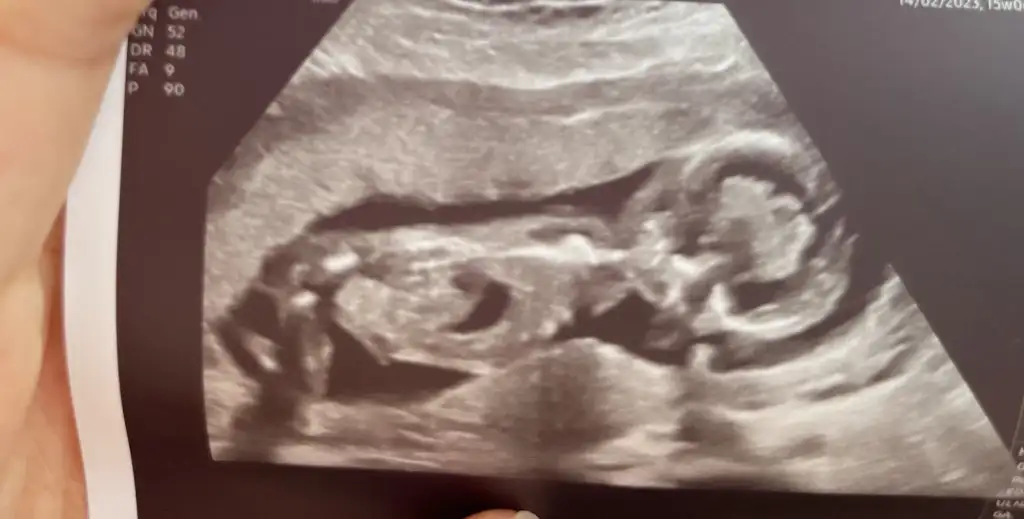

Sizce cinsiyet nedir 15 haftalık oldu bir türlü öğrenemedim düzgün durmuyor en son kıza benziyor dediler çok merak ediyorum